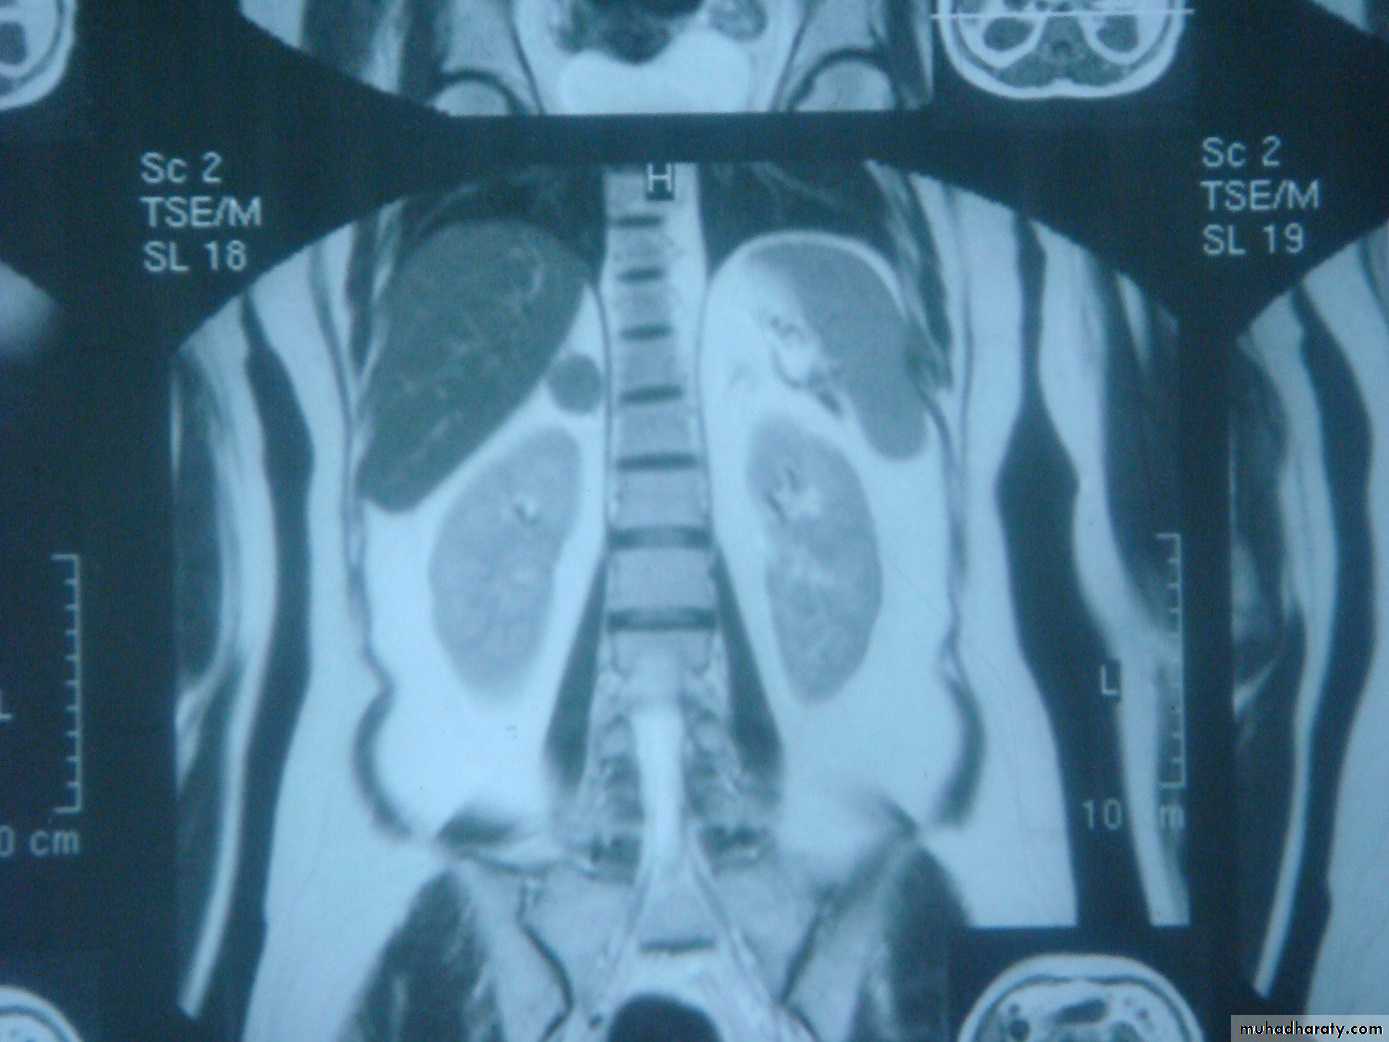

MRI or CT should be performed to distinguish unilateral from bilateral disease

In patients with suppressed ACTH levels, a CT or MRI scan is performed to assess the adrenal glands.

2- imaging study for the localization of the phaeochromocytoma and/or metastases. MRI is preferred because contrast media used for CT scans can provoke paroxysms.

CT/MRI of the chest and abdomen, a bone scan.

3-MRI and CT are equally effective in distinguishing adrenocortical adenoma from carcinoma